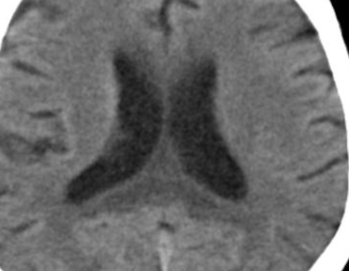

CT

- Hypoatténuation dans le corps calleux